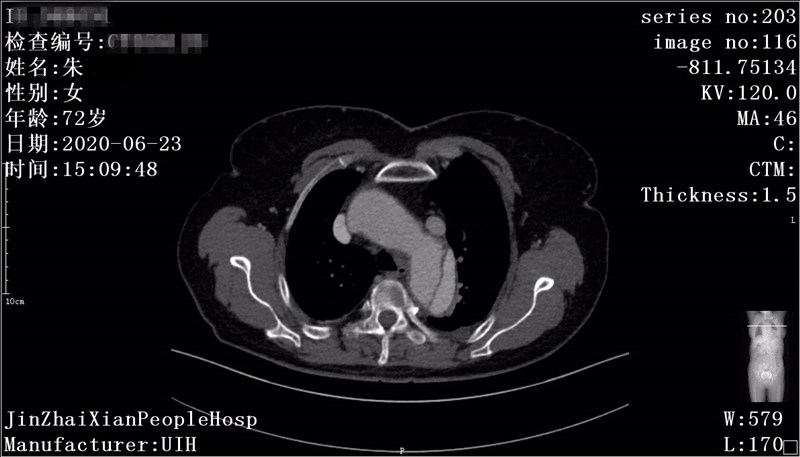

患者朱某,女,72岁,家住我县全军乡,6月22日下午突发胸背部剧痛至我院急诊科就诊,行胸部CTA检查考虑主动脉夹层(Debakey  III型),急请我科会诊。会诊后以主动脉夹层收住介入科,积极给予稳定血压、镇痛治疗。因该患者为先天性失聪失语,沟通十分困难、不畅,祝国臣副主任通过患者女儿耐心与患者沟通,详细询问病情,仔细检查患者体征,并与患者家属说明患者的病情与风险,患者家属了解病情后,十分感激祝国臣医生,决定手术治疗。我科积极完善相关术前准备及手术所需材料,于 7月5日在DSA下行“主动脉、左锁骨下动脉造影+分支型覆膜支架腔内隔绝术”,术中患者破口及真假腔显示明确,破口位置与左锁骨下动脉距离较近,给手术带来一定的困难,根据患者术中造影情况,制定详细手术方案,既保证覆膜支架安全成功释放,又保证不影响左锁骨下动脉血供。术后患者病情平稳,现患者血压、心率稳定,患者胸背部疼痛症状消失。

术前CT显示主动脉夹层真假腔及破口位置